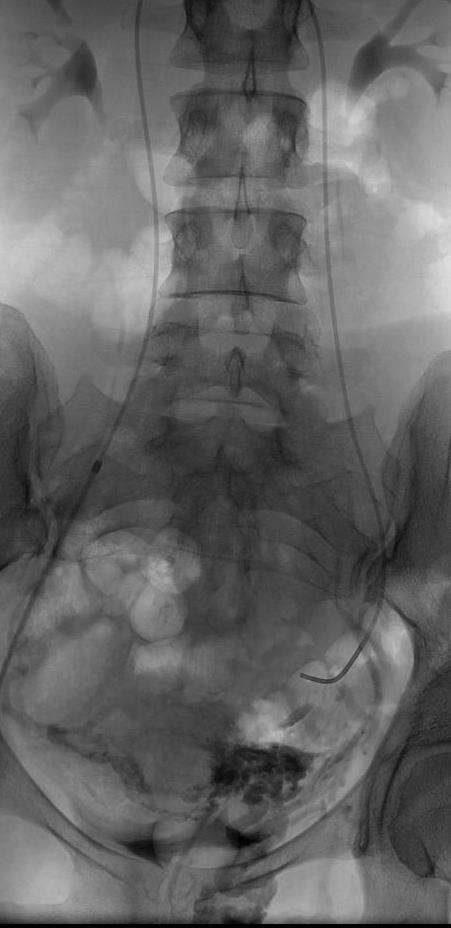

四、术前造影 现代介入放射学的进展已经使盆腔充血综合症的治疗得到彻底的改观【3,4】。首先卵巢静脉造影技术已经成熟。通过向左、右卵巢或\和髂内静脉选择性造影,可以清楚地观察静脉结构。 在任何治疗之前诊断是第一位的。静脉造影要观察 1. 是否生殖静脉逆流(Down gonadal vein); 2. 生殖静脉分支(Branches of gonadal vein); 3. 不常见的静脉(unusual veins); 4..跨越盆腔到对侧的静脉(Cross-pelvic collaterals)以及 5. 进入到会阴或狭窄的静脉曲张。 6. 而对静脉大小的观察与决定栓塞的方式相关。

卵巢静脉的不常见的异常分支

球囊闭塞髂静脉造影用于确定是否存在髂内静脉曲张。相对而言卵巢静脉显影往往需要一根同轴选择性导管而非球囊闭塞导管。静脉造影可以确定卵巢和盆腔静脉是否存在曲张,也为下一步进行影像学引导下治疗,例如经导管栓塞术,提供了基础。由于从盆腔来的静脉血流速度很快,所以在静脉造影后,需要后续的双侧髂内静脉球囊闭塞。闭塞球囊扩张后,避免造影剂回流,这样就可以使髂内静脉的显影更加清楚。

如果可能,病人应该在卧位和半立位各进行一次选择性置管左右卵巢和髂内静脉造影。在卧位和立位时静脉内径变化可能过大,例如病人在立位时曲张的静脉可能过度充盈,而这个体位可以去除这个因素而更好的判断静脉曲张的程度。但是由于导管室造影台的设计以及为病人安全的考虑,一般很难做到上述要求。在女性中使用的经导管栓塞技术与在男性中使用的是相似的,唯一不同的是不能防止性腺暴露于放射线下,因为没法在技术上将卵巢屏蔽起来。因此必须尽可能减少病人接受的荧光放射线和X线。